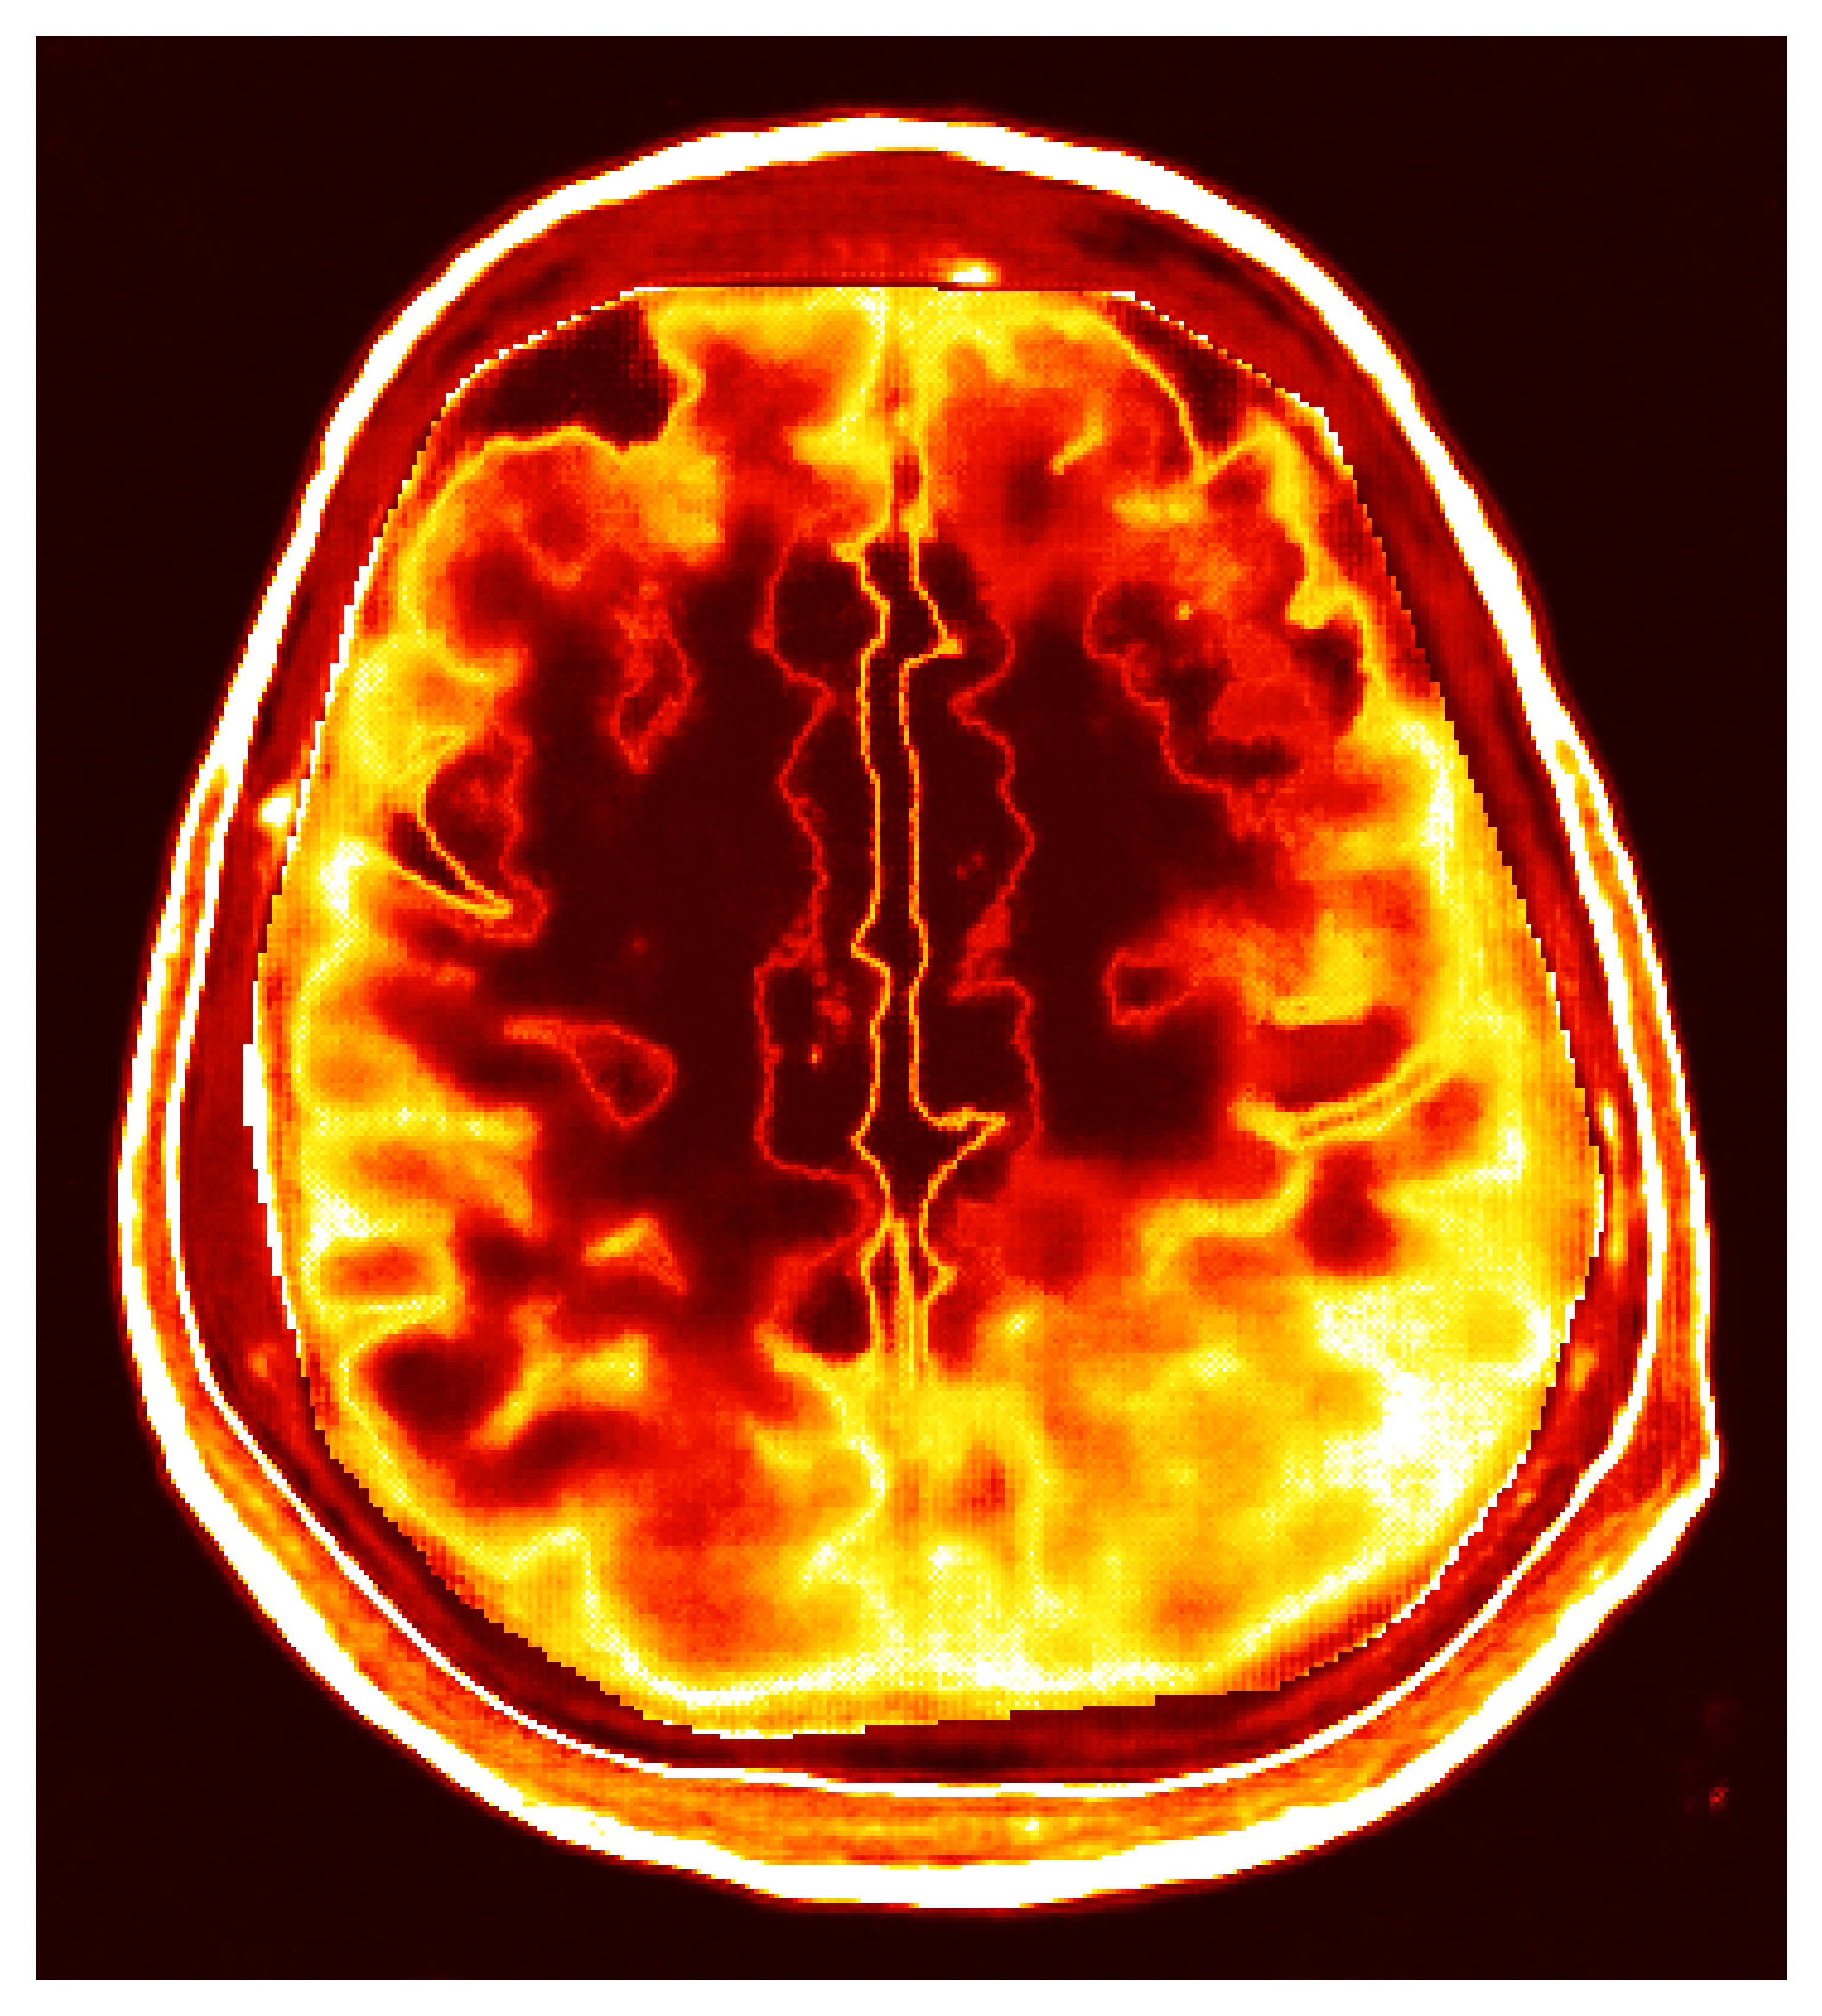

Inverse problems are fundamental to numerous scientific and engineering fields, wherein one seeks to infer causative factors from observable effects. The central challenge in inverse problems is that they are often ill-posed; the solutions may not exist, be non-unique, or depend discontinuously on the data. This ill-posedness demands sophisticated mathematical techniques to ensure stable solutions and to explore the family of solutions that can explain the data. The example we treat practically involves challenging medical imaging, where internal structures of the human body (the brain) are inferred from ultrasound measurements through the skull seen in Figure 1. The importance of fast and reliable solutions in this application cannot be overstated as they directly influence possibly life saving diagnostic decisions.

Transcranial Ultrasound Computed Tomography (TUCT) is a non-ionizing, non-radiative imaging modality that creates images of brain tissue from measurements of impinging ultrasound waves due to contrast in tissue acoustic properties. Unlike other ultrasound imaging targets, like breast imaging [44, 45], TUCT faces the challenge of high acoustic contrast in the cranial bone, leading to scattering unsuitable for traditional traveltime tomography methods [46]. Tomographic methods require high frequencies for higher resolution imaging, but attenuation through the skull is exacerbated at higher frequencies thus preventing high-resolution imaging when relying on traveltime methods. This challenge has hindered ultrasound’s application to brain imaging until recent developments when [47] identified that similar challenges exist in transcranial ultrasound imaging as with sub-salt imaging used by exploration seismology. The main reason seismic techniques are capable of imaging through high-acoustic contrast salt is because these sophisticated inversion methods model the full physics of the wave equation to make sense of the scattered waves. Whereas traditional ultrasound only uses arrival times, seismic imaging techniques model all waveforms allowing for higher effective resolutions at lower frequencies that experience less attenuation through the skull. These methods are denoted Full-Waveform Inversion (FWI) since they model and match the full observed waveform, see Figure 6 for an example of the full waveform.

4.1 Medical ultrasound with full-waveform inversion

Since the groundbreaking work of [47], FWI techniques for TUCT are showing promise as a high-resolution imaging modality with potential clinical applications ranging from early hemorrhage diagnosis to tumor imaging [48, 49]. The TUCT inverse problem involves reconstruction of the acoustic velocity, , of brain tissue from acoustic data, , collected as shown in Figure 6. In this setup, ultrasound transducers placed around the patient’s head perform multiple experiments, with each involving a tone-burst transmission by one transducer and recording by all others, as simulated in Figure 6. Experiments proceed by transducers transmitting from different positions until all transducers have transmitted, providing a full coverage from many angles. The forward operator that maps the acoustic parameters to the observed data is simulated with the numerical solution of the second-order wave equation with varying acoustic velocity in two space dimensions:

Our synthetic TUCT experiment, based on the configuration from [47], models the unknown parameter as discretized acoustic velocity on a grid, with a discretization. We modeled transducer sources as point sources with a three-cycle tone-burst signature with central frequency of and [microseconds] recording time. The transducers are placed in a circular arrangement around the skull, the setup, with sources and receivers, mimics a 2D slice of the 3D experiment shown in Figure 6. The forward operator, , corresponds simulating the forward waveforms and their restriction to the receiver locations. The wave equation and its Jacobian were solved using the open-source software packages Devito and JUDI [58, 59, 60], which automatically generate optimized C code and leverage GPU accelerators, thereby facilitating scalability to realistic problem sizes. To simulate noise corruption, we used additive Gaussian noise, , with a Signal-Noise-Ratio, matching lab values [47]. A synthetic observation, , is displayed in Figure 6.

4.3 Traditional amortized inference

To illustrate the limitations of amortized VI, we train a CNF on pairs without evoking iterative improvements by ASPIRE. We emphasize that the observations are the raw unsummarized waveforms similar to that shown in Figure 6. Training details are included in Section \thechapter.C. After training by minimizing Equation 3, the CNF with weights , provides an amortized approximation of the posterior, , from which we can sample (cf. Equation 4). The results, shown in Figure 7, demonstrate that the samples from , for an unseen test observation, , lack distinct features beyond an unrealistic skull and unresolved internal tissue structure. A comparison of these samples and the posterior mean, , in Figure 7 with the ground truth, Figure 7, highlights the poor quality of this approximation. Note, throughout this exposition we calculate the posterior statistics (i.e. mean and standard deviation) over samples, please consult the Section \thechapter.E for a discussion on this quantity. This experiment underscores the challenge of directly learning the probabilistic inverse mapping from the acoustic data to the velocity parameters, a difficulty previously noted in the literature [63]. This challenge is often referred to as the ‘end-to-end’ problem [64]. We address this problem with the score-based summary statistic employed by ASPIRE.